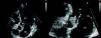

Case reportA 50-year-old man with a history of smoking, drug addiction and chronic hepatitis C went to the emergency department with asthenia, fever and headache of one month's evolution and abdominal pain for two days. On physical examination he presented fever; cardiac auscultation revealed a loud decrescendo diastolic murmur, grade III/VI, at the left sternal border; there were no signs of heart failure. Laboratory tests revealed acute renal failure (creatinine 2.5mg/dl and urea 60mg/dl compared to normal values one week previously), elevated C-reactive protein (77.5mg/l) and normocytic normochromic anemia (Hb 11.2g/dl). Abdominal computed tomography (CT) showed splenomegaly without visible infarcted areas and right hydrouretonephrosis caused by an aneurysm of the right common iliac artery (42mm maximum diameter). Transthoracic echocardiography (TTE) revealed a 15-mm vegetation on the non-coronary leaflet of the aortic valve (Figure 1) and severe aortic regurgitation (Figure 2), together with moderate to severe left ventricular systolic dysfunction (ejection fraction 35%); these findings were confirmed by transesophageal echocardiography. The patient was admitted to the cardiology department, where empirical antibiotic therapy was begun with vancomycin and meropenem; it was decided not to add an aminoglycoside due to his low glomerular filtration rate, estimated at 20ml/min/1.73m2. On the second day of hospital stay he showed signs of cognitive slowing, with no focal neurological alterations; subsequent cerebral magnetic resonance imaging (MRI) showed multiple recent cerebral infarcts. Amphotericin B-susceptible Candida albicans was isolated from blood cultures; antifungal therapy was begun and the surgical center was contacted in order to transfer the patient for aortic valve replacement. While awaiting transfer, he suddenly suffered intense pain, coolness and loss of pulses in his left leg due to acute ischemia, probably caused by cardioembolism from the fungal vegetation. He was transferred urgently to a vascular surgery center where distal left patellofemoral embolectomy was successfully performed. The patient was then transferred to the cardiothoracic center and the aortic valve was replaced by a bioprosthetic valve. Microbiological analysis of the aortic valve and the embolus removed from the left femoral artery revealed C. albicans. Postoperative TTE showed normal aortic prosthetic valve function and after 14 days the patient was transferred to the cardiology department of our hospital. During hospitalization he presented fever and elevated inflammatory markers; repeat TTE confirmed normal prosthetic valve function, with no evidence of vegetations. MRI of the abdomen and lower limbs detected a large pseudoaneurysm of the right iliac artery, the external iliac artery being occluded distal to the pseudoaneurysm, multiple swellings compatible with abscesses in the left groin and thigh (the access site for the previous vascular surgery), and abscesses in the anterolateral muscle compartment of the left leg (Figure 3). In view of the existence of a focus of infection and the absence of evidence of endocarditis on TTE, it was decided not to perform transesophageal echocardiography. The patient was transferred to the vascular surgery department, where he underwent total aneurysmectomy with femoro-femoral crossover bypass using an inverted right greater saphenous vein graft, together with exploration and drainage of the abscesses in the left leg. Microbiological study of the pseudoaneurysm revealed Staphylococcus epidermidis. During hospitalization in the vascular surgery department intermittent fever persisted and the patient's general condition progressively deteriorated. S. epidermidis was detected in repeat blood cultures and broad-spectrum antibiotic therapy was begun with vancomycin and meropenem. CT of the pelvis and thighs revealed two new pseudoaneurysms, in the left internal iliac artery and the left superficial femoral artery. The patient underwent further surgery, during which it became clear that the clinical situation had progressed rapidly, with rupture of the left femoral pseudoaneurysm and extensive hemorrhagic infiltration and abscesses in the thigh. The left internal iliac and left superficial femoral arteries were ligated and devitalized tissue and purulent collections were thoroughly debrided. Late in the procedure it was decided to proceed to open transfemoral amputation of the leg, due to gangrene. The patient remained in the vascular surgery department for four months, during which antifungal therapy was maintained; transfemoral reamputation was performed and surgical debridement of abscesses in the stump were required on several occasions. After partial closure of the residual limb he was discharged, clinically stable; it was decided not to continue antifungal therapy due to its possible hepatic toxicity and the patient's chronic hepatitis C.